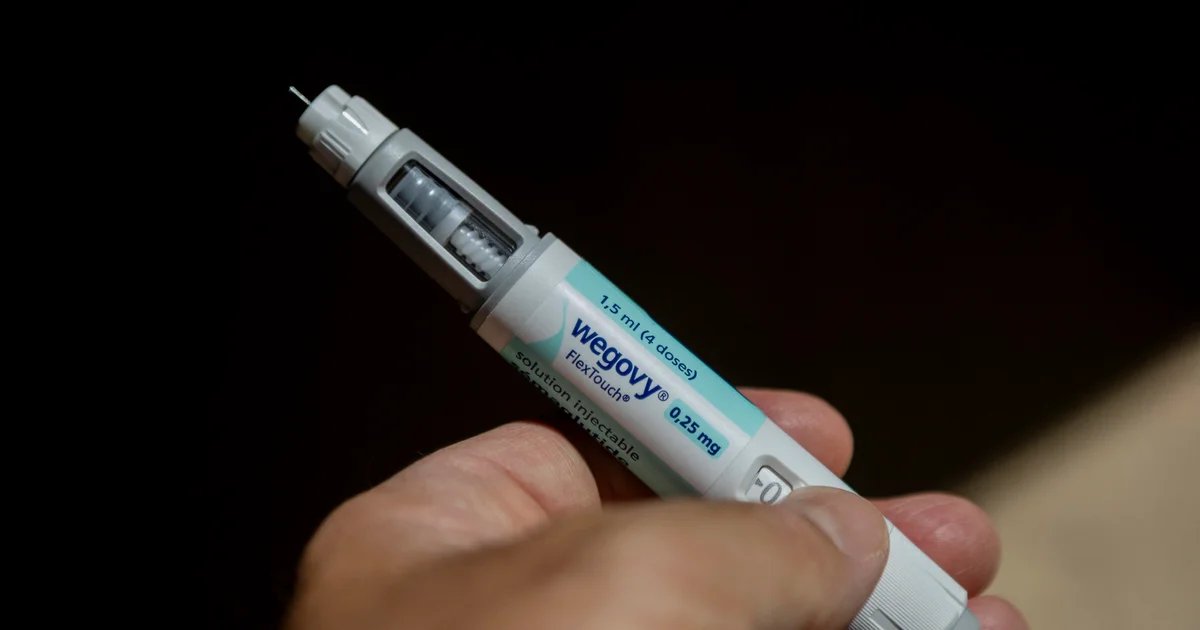

Scientists reveal why a popular anti-aging compound may also fuel cancer

Polyamines are naturally produced molecules present in all living cells. They play a vital role in basic biological functions, including cell growth and specialization. In recent years, scientists have focused…